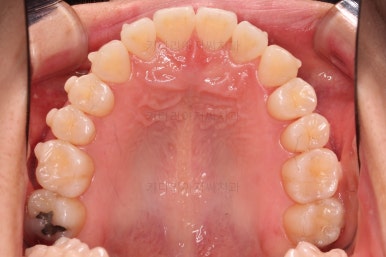

삐뚤한 덧니를 가지런하게 하기 위해서 필요한 부분의 어금니를 순차적으로 뒤로 밀어줍니다.

자세히 보면 치아 사이사이에 틈새가 생기는게 보이죠?

틈새를 일부러 만들어 해당 공간으로 덧니를 가지런하게 하는 원리입니다.

장치를 사용한지 1년 2개월째 사진입니다.

매우 가지런해졌죠.

매우 가지런해졌고요.

맞물림도 좋아졌고, 중앙선도 잘 맞춰졌습니다.